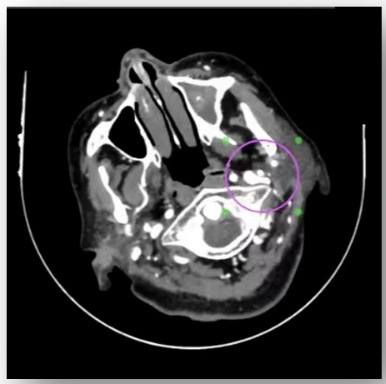

术前颈椎CT

通过高分辨率颈静脉超声及CT静脉造影(CTV)检查,清晰显示患者左侧颈静脉存在明确的受压征象,这为脑内异常血流声的产生提供了解剖学依据。为确保诊断的精准无误,在科室的大力支持下,哈医大一院神经外科学科主任史怀璋教授和神经外科三病房主任徐善才教授亲自为患者进行了全脑血管造影(DSA),对检查结果进行研判,并与神经外科二病房主任杨光教授、程玉教授共同分析患者病情。DSA作为血管诊断的“金标准”,进一步证实了颈静脉的受压情况,并排除了其他颅内血管畸形,为后续手术提供了安全保障。在综合所有检查结果并进行详尽的术前讨论后,团队明确诊断患者为“脑鸣综合征”,其根本病因在于颈静脉机械性受压。